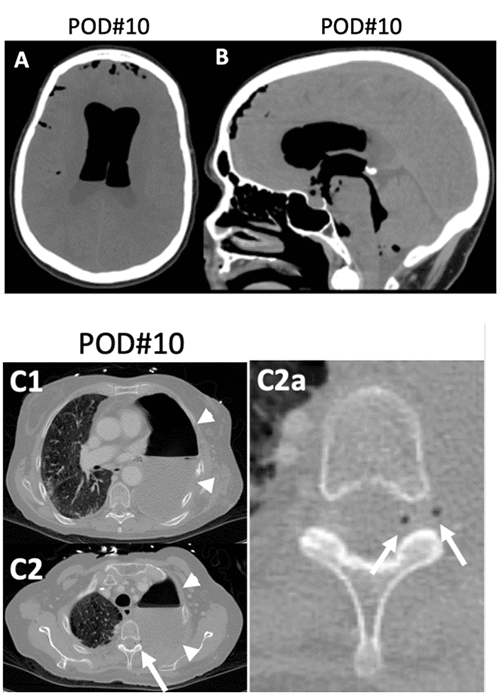

On POD 10, the neurology team was emergently consulted due to progressive mental status decline and headaches. Examination revealed a Glasgow Coma Scale (GCS) score of 9, global aphasia, conjugate gaze, and absent blink reflex to threat. Corneal reflex was intact. Upper extremity pain localization was present, but lower extremity response was limited to withdrawal. Non-contrast head CT scan demonstrated intraventricular and subarachnoid pneumocephalus with mild-to-moderate hydrocephalus (Figure 2).

Given the initial suspicion of a subarachnoid-pleural fistula as the cause of pneumocephalus, a chest CT was obtained on the same day. The CT revealed an air- and fluid-filled cavity from a left thoracic pneumonectomy, along with two small areas of air density located within the left T2/T3 foramina and the left side of the spinal canal. These findings were supportive of a subarachnoid-pleural fistula; however, additional investigations were warranted for confirmation.

Figure 2. Pneumocephalus Secondary to Subarachnoid-pleural Fistula on POD 10. Published with Permission

A, B: Axial and sagittal head CT scans demonstrate extensive intraventricular and subarachnoid air (pneumocephalus). C1, C2: Axial chest CT scans on the same day reveal an air- and fluid-filled left thoracic cavity post-pneumonectomy (arrowheads). C2 (white arrow): Punctate air foci within the left T2/T3 foramina and the spinal canal indicate a subarachnoid-pleural fistula. This is magnified in the inset (C2a, white arrows)